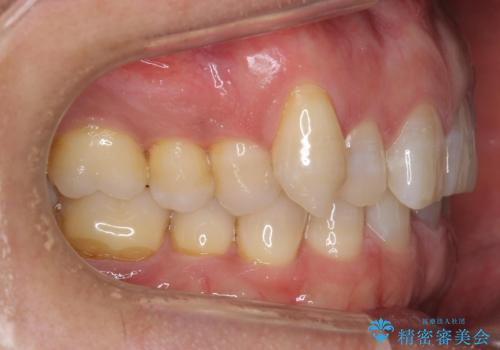

- 右上の犬歯が目立つのが気になる、下の歯並びも治したいとのことで来院。

右上の犬歯の歯肉退縮自体は進行する可能性をお伝えしておりましたが、特に変化なく治療できました。

歯肉退縮につきましては、歯ぐきの移植を提案しましたが特に希望されませんでした。